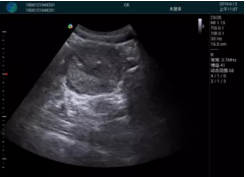

病例一:

清晰顯示孕囊,通過軟件包計算孕齡7w+6d

M20實時引導(dǎo),術(shù)中清晰顯示孕囊被破壞和抽吸針的過程,清晰顯示吸引針

抽吸結(jié)束后縱切子宮,孕囊已被完全抽吸,未見明顯殘留

橫切子宮,發(fā)現(xiàn)右側(cè)宮腔靠近宮角處有少許脫模樣殘留

M20引導(dǎo)下,抽吸針找到右側(cè)宮角處再次清掃

二次抽吸后再次進行超聲檢查,宮腔未見殘留,宮腔線清晰顯示

超聲引導(dǎo)下可視化人流是技術(shù)安全性的保障,一般對人流術(shù)設(shè)備預(yù)算不高,M20具備婦產(chǎn)科軟件包,且穿透力圖像質(zhì)量好,既滿足人流引導(dǎo)需要,也可用于床旁超聲的需求。